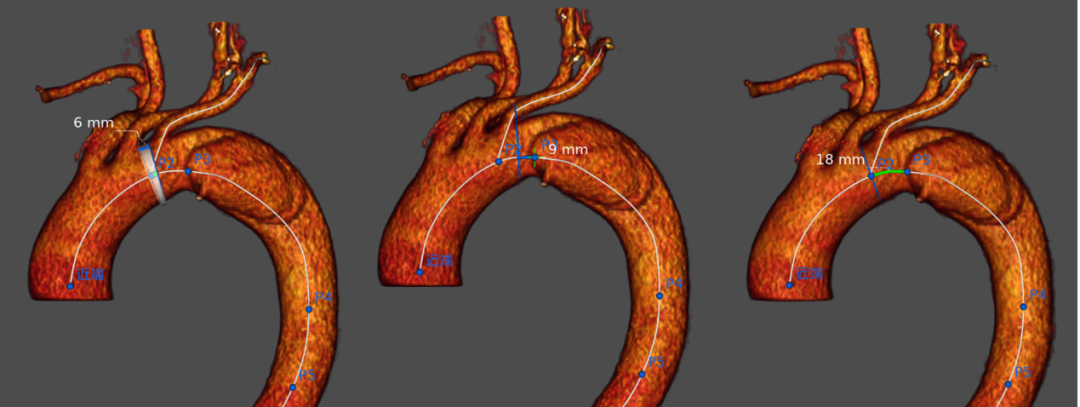

下半场第一台手术仍然由南京大学医学院附属鼓楼医院的周庆主任主刀。患者是一名73岁的老年女性,2周前因“突发剧烈胸背部疼痛3小时余”,外院明确为“Stanford B型主动脉夹层”转诊收住。既往有高血压病史20年,血压控制欠佳。经CTA充分评估,结合患者病情及实际情况,拟行胸主动脉覆膜支架植入+LSA体外开窗重建术。

术中右侧腹股沟切开游离股动脉(置入6F鞘管),左肱动脉穿刺置入5F鞘管。经右侧股动脉鞘管送入5F猪尾导管行主动脉造影,显示降主动脉夹层形成,内膜破口位于弓降部小弯侧,距左锁骨下动脉开口约3cm,取先健Ankura胸主动脉支架,体外部分释放,在第二节背侧开窗,直径约1.4cm,重新装载后沿导丝送入,推送支架近端置于左颈总动脉开口后缘,经左肱动脉鞘管置入猪尾导管再次造影确认支架位置。将动脉收缩压调整至100mmHg以下,释放支架。再次行主动脉造影,显示支架形态良好,未见内漏,左颈总动脉显影、左锁骨下动脉显影。

周庆教授完整详细的演示了Ankura支架应用于TEVAR手术中锁骨下动脉的血运重建,并在对体外开窗技术的操作要点进行了详细阐释。